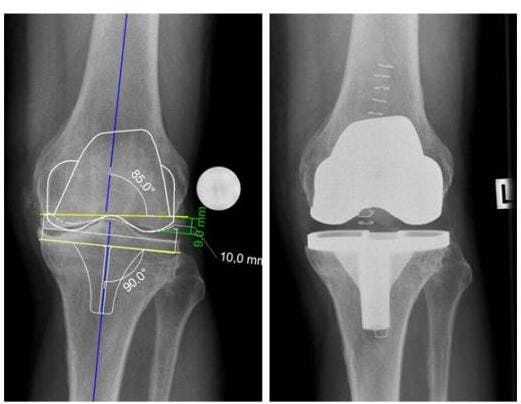

PROTHESENPLANUNG

Röntgenbild Prothesenplanung Knie

Die Prothesenimplantation wird anhand eines digitalen Röntgenbildes geplant (links), das Röntgenbild rechts zeigt die zugehörige Implantatlage eines bikondylären Oberflächenersatzes nach der Operation. (Bilder: Orthopädie)